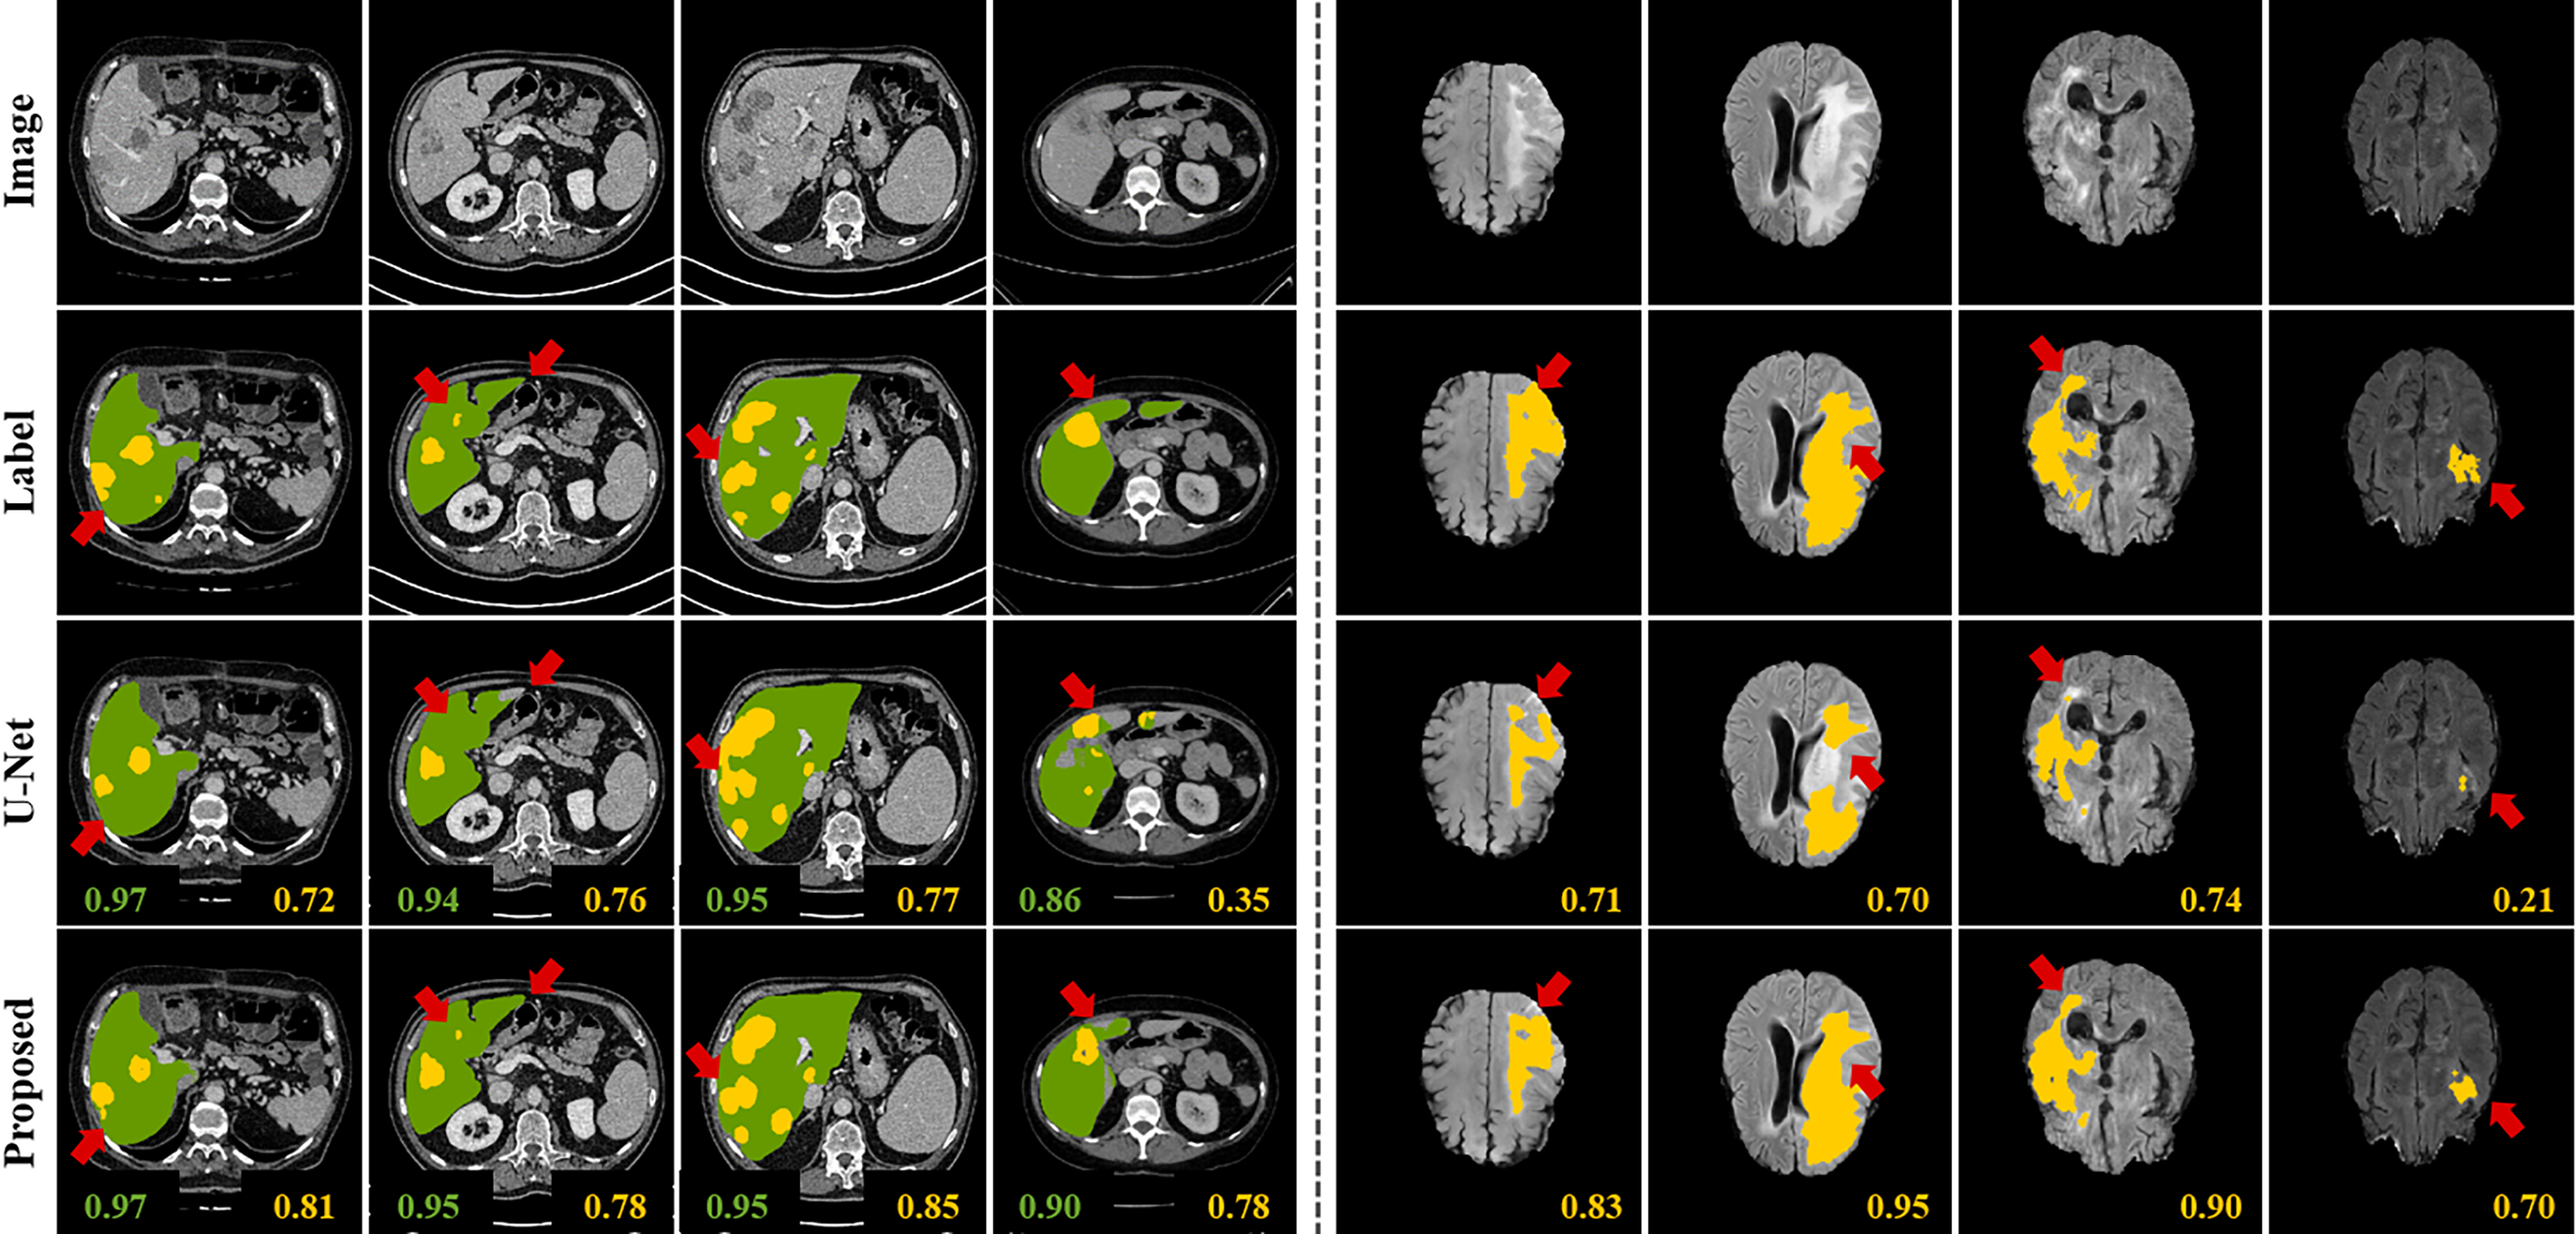

Figure 4: Qualitative comparison results of the semi-supervised tumor segmentation. Left: results from our method using 1/10 labeled data on the LiTS dataset (green: liver, yellow: tumor). Right: results from our method using 1/4 labeled data on the BRATS dataset (yellow: tumor). First row: center slices of input. Second row: ground-truth labels. Third row: results from the supervised learning method [10] by CEsubscript𝐶𝐸\mathcal{L}_{CE}. Fourth row: results from our semi-supervised learning algorithm using CEsubscript𝐶𝐸\mathcal{L}_{CE} and MScnnsubscript𝑀𝑆𝑐𝑛𝑛\mathcal{L}_{MScnn}. The scores on the bottom of each results denote Dice score.

V-B2 Qualitative Evaluation

Fig. 4 illustrates predicted liver lesion segmentation maps from CT slices and tumor segmentation maps from MR scans. These results verify that the Mumford-Shah loss enables the network to detect boundary of tumor region in more detail. Also, there are several cases that the original deep network produces the segmentation map with the IoU score less than 0.5 but with the same network our proposed loss function improves the results with the IoU score of higher than 0.7. Since the Mumford-Shah loss functional is computed with pixel-level information, we observed that tiny and thin tumors, which are hard to be distinguished with surrounding area, can be clearly segmented in our method.